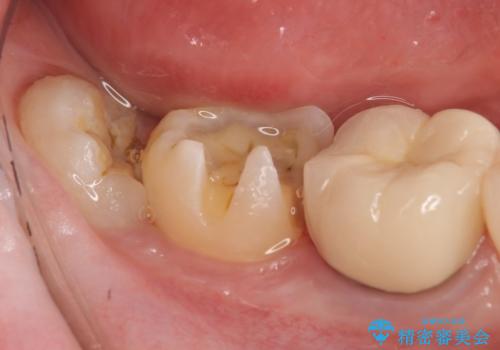

- 右下7の銀歯を白くしたいといらっしゃった方の症例です。

銀歯及び虫歯を除去後、セラミックインレーで修復を行いました。